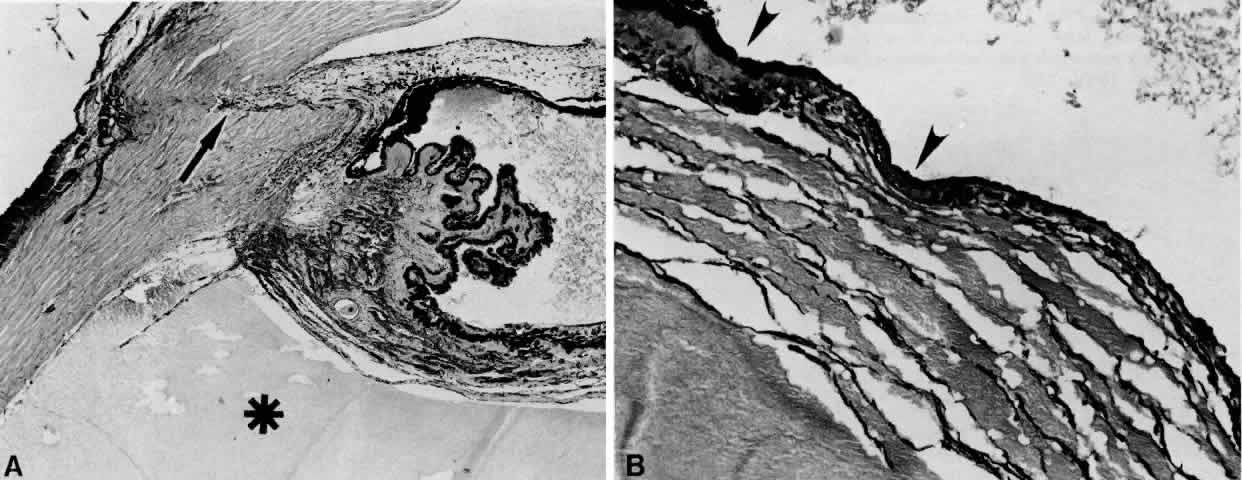

Various uveitides,60–63 including syphilitic uveitis,64 sympathetic ophthalmia (Fig. 12),65–67 toxoplasmosis (Fig. 13),65 rheumatoid arthritis,68 pars planitis,69,70 and Vogt-Koyanagi-Harada syndrome,71 may be associated with the collection of suprachoroidal fluid. In Vogt-Koyanagi-Harada syndrome, a diffuse, bilateral uveitis may lead to an exudative choroidal effusion and secondary nonrhegmatogenous retinal detachment. In addition to associated extraocular clinical features (e.g., vitiligo, poliosis, dysacousia), the presence of pleocytosis in the cerebrospinal fluid (CSF) may help differentiate Vogt-Koyanagi-Harada syndrome from uveal effusion syndrome, which characteristically lacks pleocytosis.

Fig. 12. A ciliochoroidal effusion in the eye of a 16-year-old boy, who developed sympathetic uveitis after a corneal laceration. A. Scar of the traumatic corneal perforation, with fibrous tissue ingrowth (asterisk) and adherent lens remnants (arrowhead) (H & E, × 18). B. The appearance of a ciliochoroidal effusion (asterisk) that was first observed in the eye 2 months after corneal perforation and before the development of uveitis in the fellow eye (H & E, × 96). C. The choroid posteriorly is greatly thickened by intense lymphocytic infiltration in which foci of epithelioid cells (arrowheads) display pigment phagocytosis in the absence of necrosis (H & E, × 185).

Fig. 13. A. A ciliochoroidal effusion (asterisk) associated with Toxoplasma retinochoroiditis (H & E, × 50). B. The retina temporally is totally necrotic with encysted T. gondii (H & E, × 25). C. An old chorioretinal scar (arrow) posterior to the area of necrotic retina (H & E, × 160). D. Intense vasculitis and perivascular lymphocytic infiltration of the central vessels in the optic nerve head (H & E, × 185).